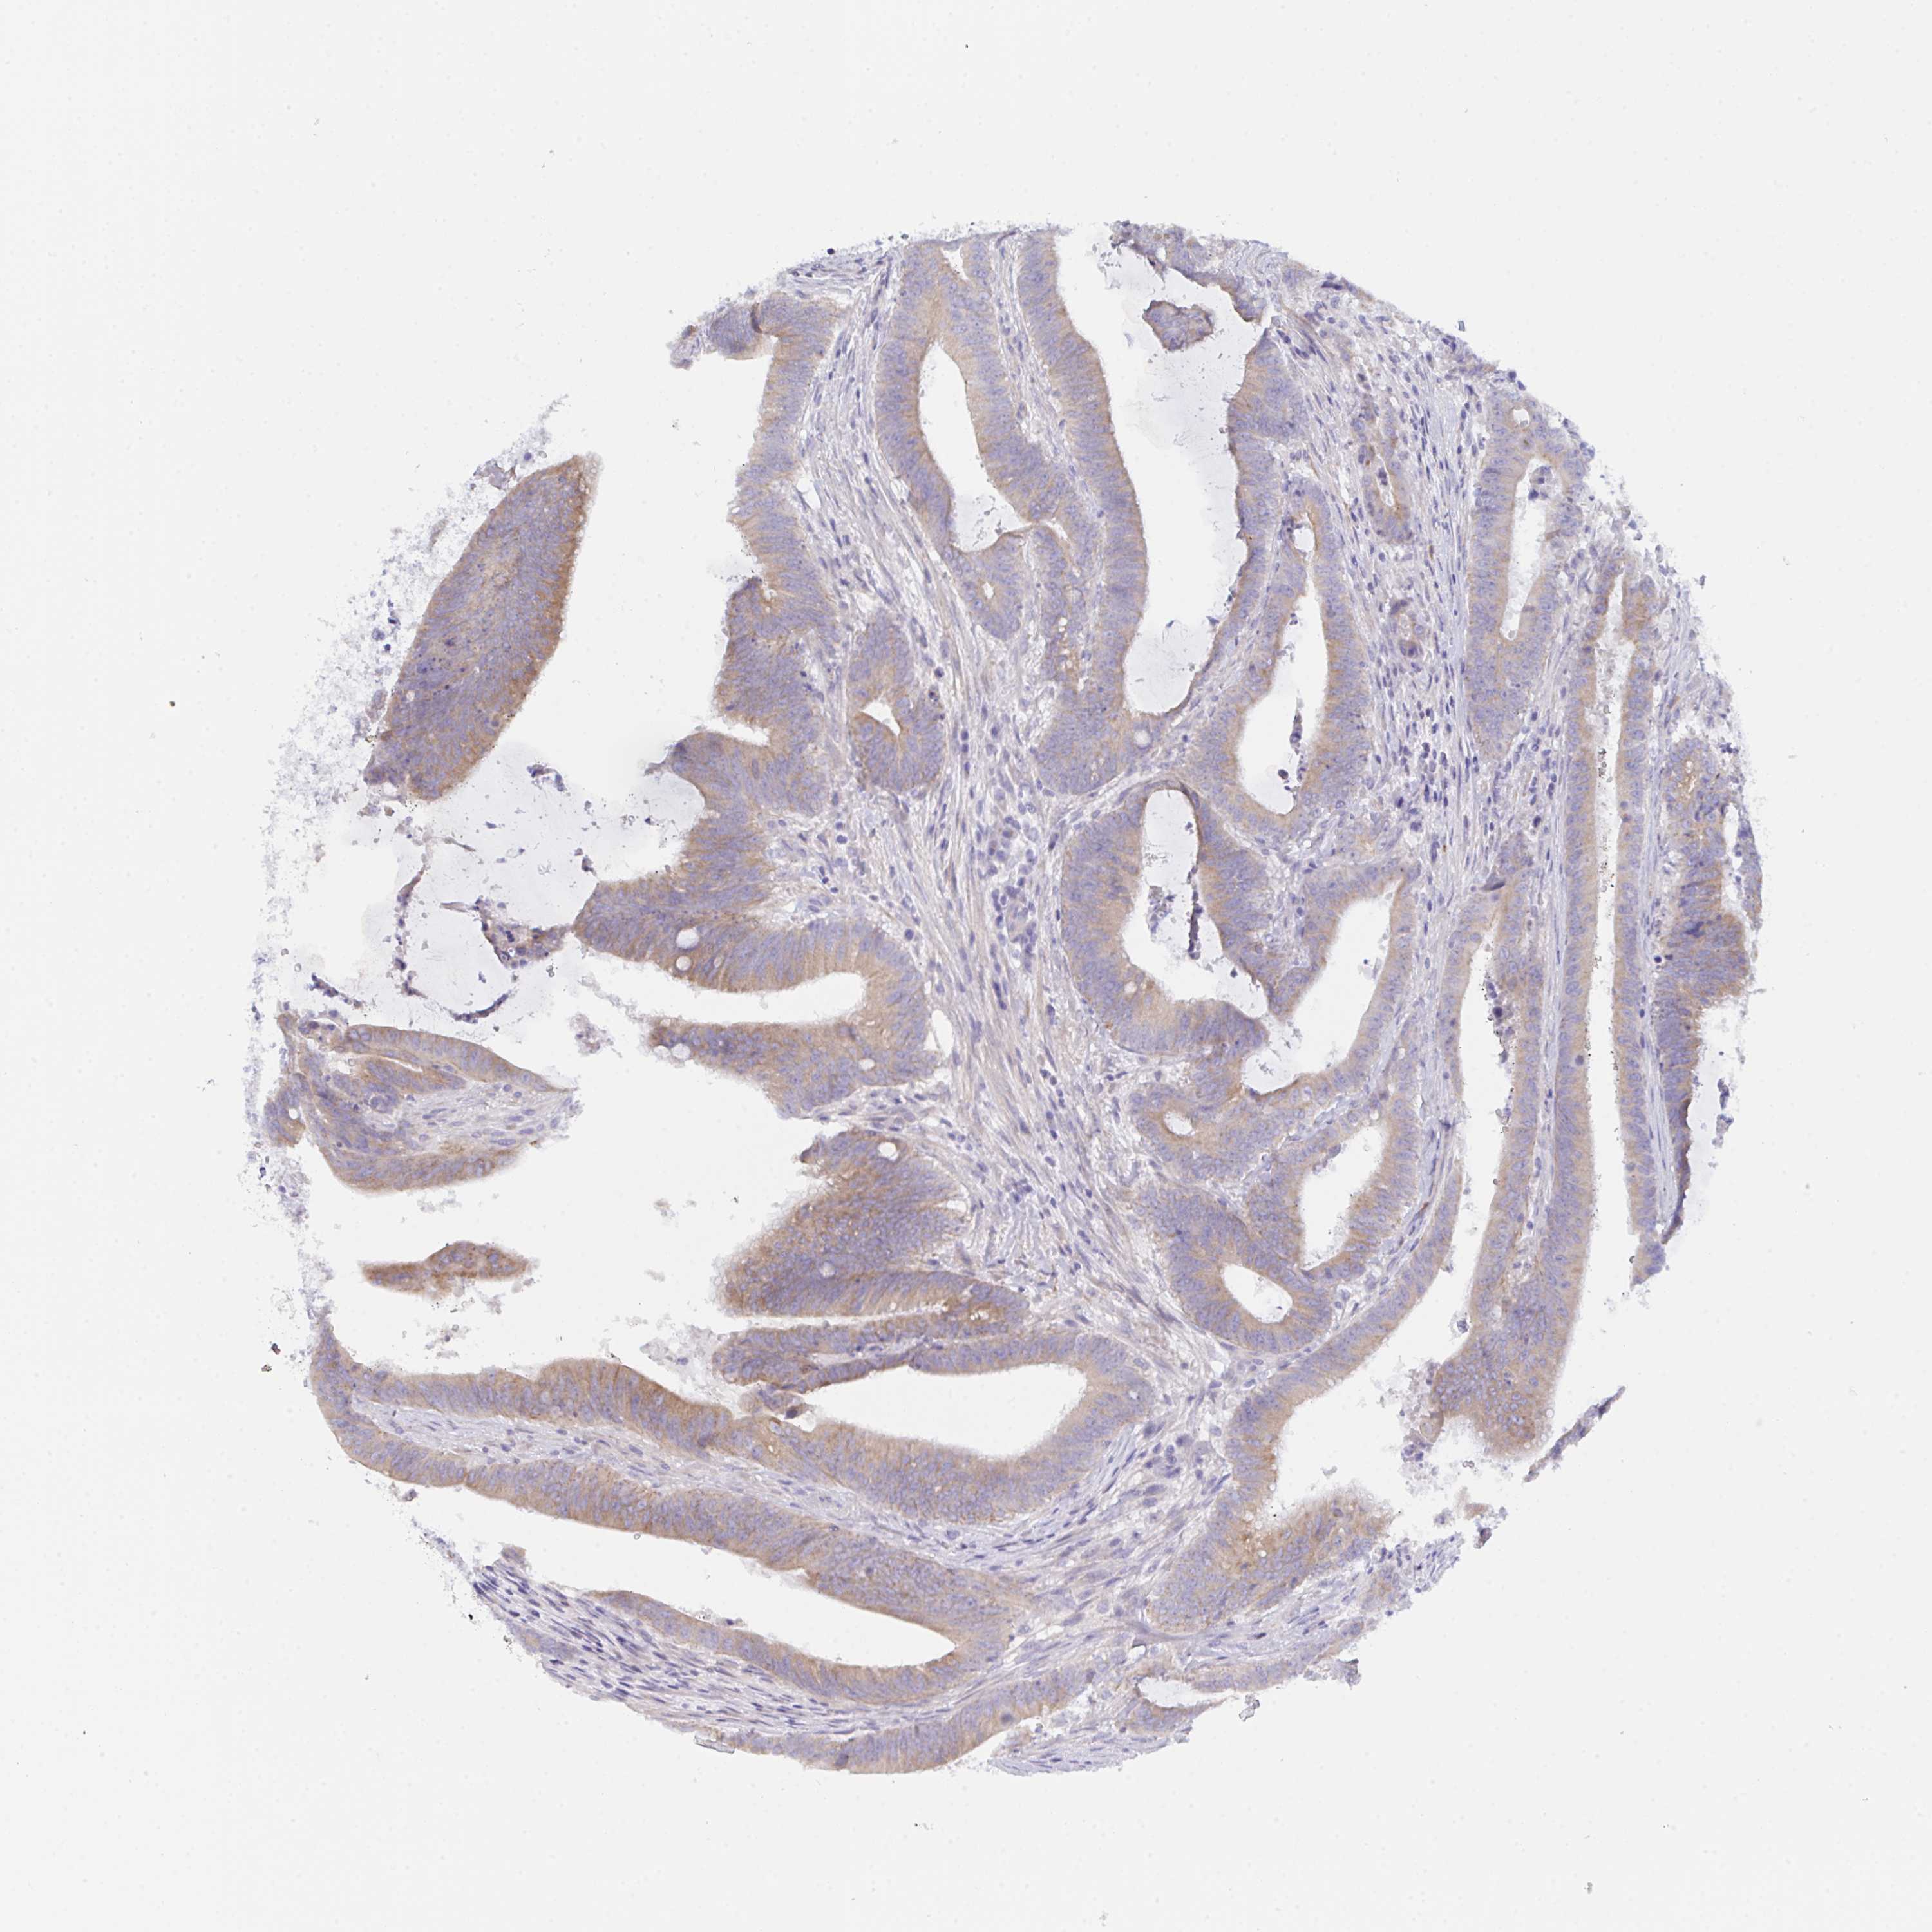

CANCER COLORECTAL CANCER Show tissue menu

Colorectal cancer

Human cancer

Colon adenocarcinoma